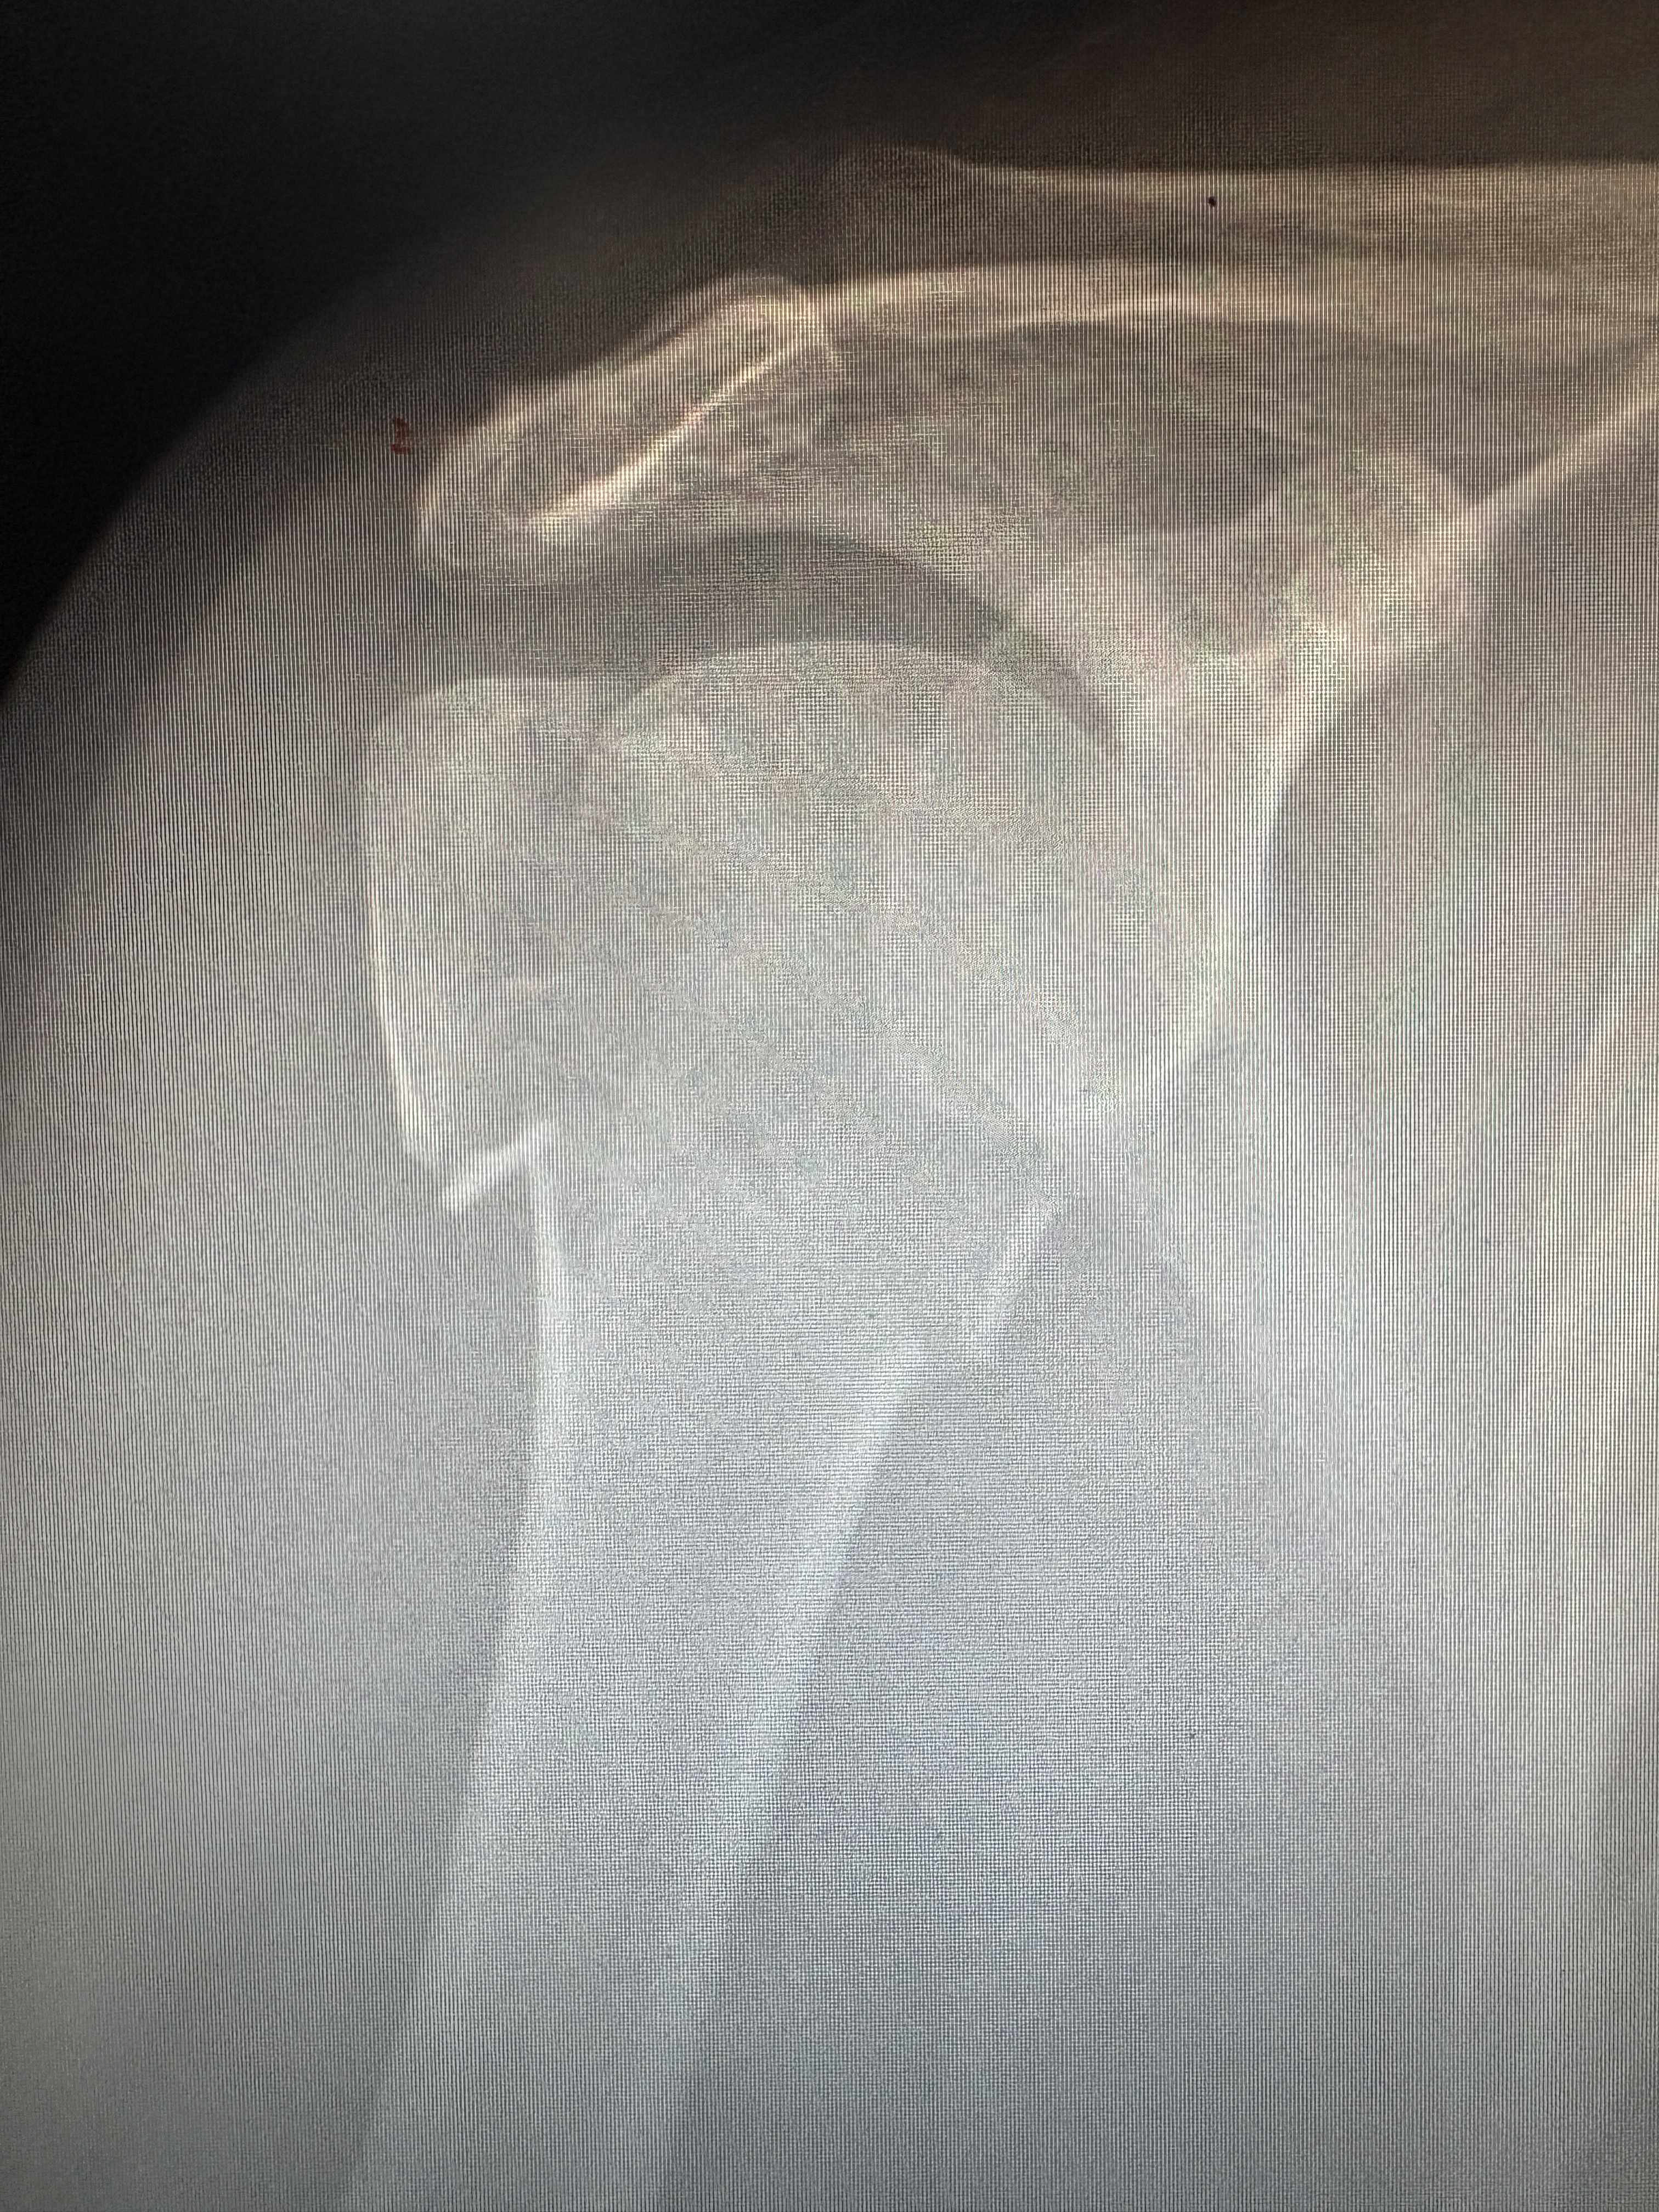

肱骨大结节骨折严重吗

1、综上所述,肱骨大结节骨折虽然是一种骨折,但通常并不严重,通过适当的治疗和康复锻炼,患者能够恢复良好的功能。 2、综上所述,肱骨大结节骨折是一种涉及肩关节稳定性的严重损伤,需要及时诊断和治疗。 3、肱骨大结节骨折以...